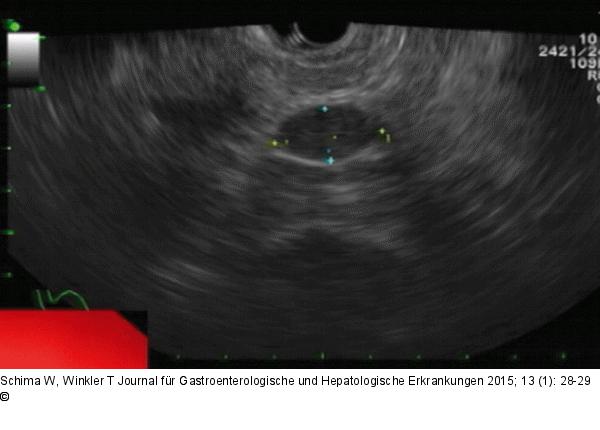

Abbildung 3: Intrapankreatische Nebenmilz Die Endosonographie zeigt gut abgrenzbar die ovale Raumforderung in der Pankreascauda. |

Die Endosonographie zeigt gut abgrenzbar die ovale Raumforderung in der Pankreascauda. |